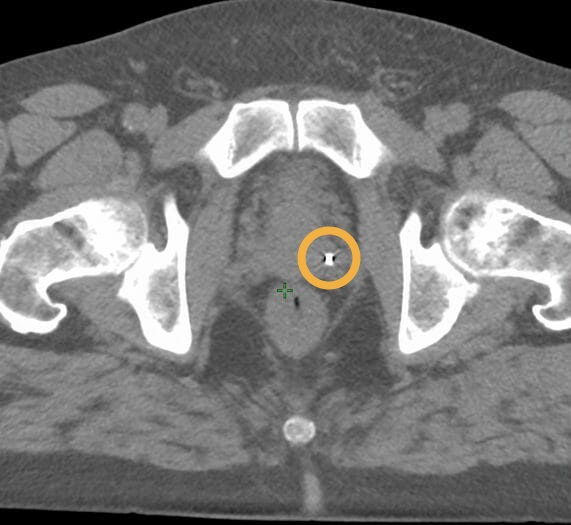

Images showing 0.4×10 mm Gold Anchor MR+ markers, implanted with a ball shape in prostate. Images courtesy of Centralsjukhuset Karlstad.

CT